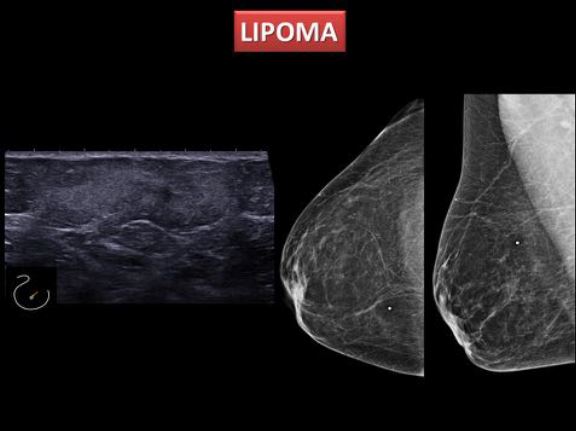

Lesiones hiperecogénicas de la mama

Amàlia González López, Viviana P. Beltrán Salazar, Sergi Ganau Macías, Amaya Martín Olóriz, Melcior Sentís Crivellé